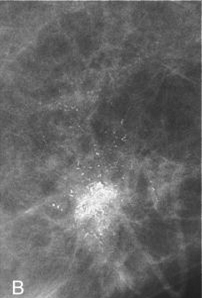

Αποτιτανώσεις υψηλής πιθανότητας για κακοήθεια (εικόνα Β)

Το πιο συχνό μαστογραφικό εύρημα που σχετίζεται με την ανάπτυξη πορογενούς καρκινώματος in situ (DCIS) είναι η παρουσία μικροαποτιτανώσεων σε ασυμπτωματικές γυναίκες. Χάρη στη διαρκή βελτίωση των διαθέσιμων απεικονιστικών τεχνικών και την ευρύτερη συμμετοχή των γυναικών στα προγράμματα προσυμπτωματικού πληθυσμιακού ελέγχου, σήμερα το DCIS αντιπροσωπεύει το 22%-45% όλων των διαγνωσθέντων καρκίνων του μαστού.

Φαίνεται ότι η μορφολογία των μικροαποτιτανώσεων έχει κάποια σχέση με την εξέλιξη, με τις υψηλής πιθανότητας για κακοήθεια αποτιτανώσεις να χαρακτηρίζουν τα high-grade DCIS, αυτά δηλαδή με υψηλό δυναμικό εξέλιξης σε διηθητική νόσο, και τις ενδιάμεσης πιθανότητας για κακοήθεια, άμορφες, να χαρακτηρίζουν μια εξελικτική διαδικασία από την άτυπη επιθηλιακή υπερπλασία ως τα low-grade DCIS, με χαμηλότερο δυναμικό εξέλιξης σε διηθητική νόσο.

Στη διεθνή βιβλιογραφία αναφέρονται προσπάθειες συσχέτισης βιολογικών προγνωστικών δεικτών των νεοπλασμάτων με τη μαστογραφική απεικόνιση των μικροαποτιτανώσεών τους, με σκοπό την καλύτερη επιλογή θεραπείας για την κάθε περίπτωση. Το βέβαιο είναι πως, παρότι μπορεί να γίνεται υπερδιάγνωση και υπερθεραπεία σε κάποιες περιπτώσεις, η πρώιμη διάγνωση και η θεραπεία είναι κομβικές.